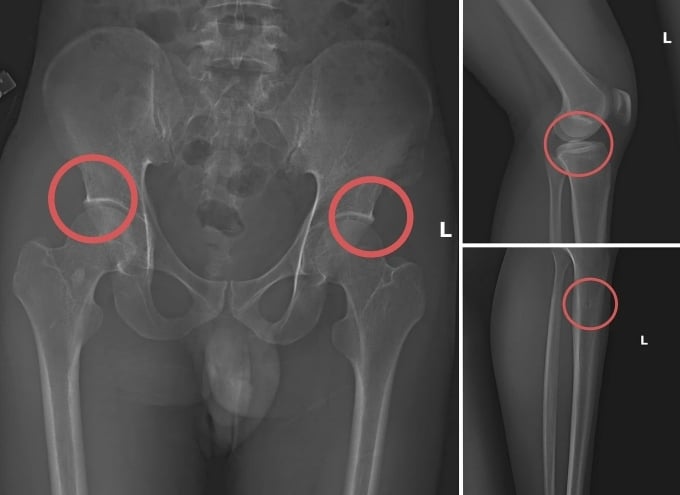

Các vết thương do nhóm đối tượng tự tạo nên. (Ảnh: Công an tỉnh Phú Thọ cung cấp).